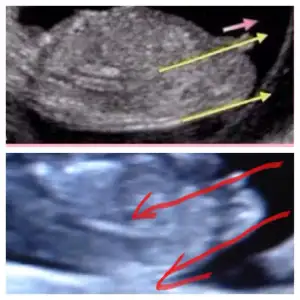

Cnm ben mı yanlıs bakıyorum acaba herkeste görüyorum kendıme görrmıyormuyum ki acaba ya offf bana paralel gelıyor baksana alttakı benım bebısım usttekı ınternette Nub fotosu bu fotoda 11 haftalık tı bebegım suan 12+5 oldumBence nub. Ve erkek bu bebis galuba.. cunku kordon olsa daha yukarda olur .. kac haftalik ?

Canm ben boyle cızdım paralel geldı ama yanlışmı bakıyorum acaba alttakı benım bebısErkeğe daha çok benzettim ben canım. Yukarı doğru açılı duruyo.

Baksana ben mı yanlıs bakıyorum canmCanim nub u paralel evet kiz olabilir..bizim ki bi tahmin..kesin olamaz..hayirli olsun canim bebeisin

Banada yorum yaparmisiniz ben kiza benzettim.. peki sizzz???